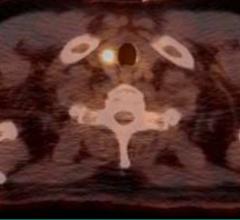

Increased radiation dose is associated with higher survival rates in men with medium- and high-risk prostate cancer, but not those at low risk, according to a new study from Penn Medicine Already-high survival rates for men with low-risk prostate cancer were unaffected by higher radiation dosages compared to lower radiation dosages, according to the study published in JAMA Oncology.